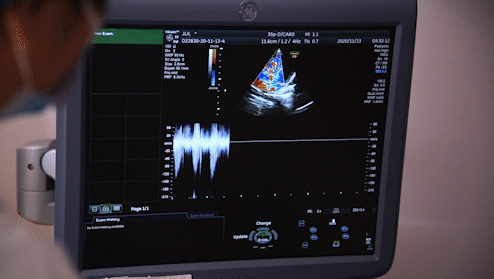

大连新百佳妇儿医院8月27日耿斌教授,胎儿心脏彩超检查。大连新百佳妇儿医院带您了解,先天性心脏病(简称先心病)是胎儿期心脏及大血管发育异常,而致的先天畸形,孕早期(5~8周),是胎儿心脏发育最重要的时期

胎儿心脏彩超,是筛查以及诊断胎儿先天性心脏病的有效手段,通过早期诊断胎儿先天缺陷,及时评估预后,对孩子、家庭和社会都有重要的意义